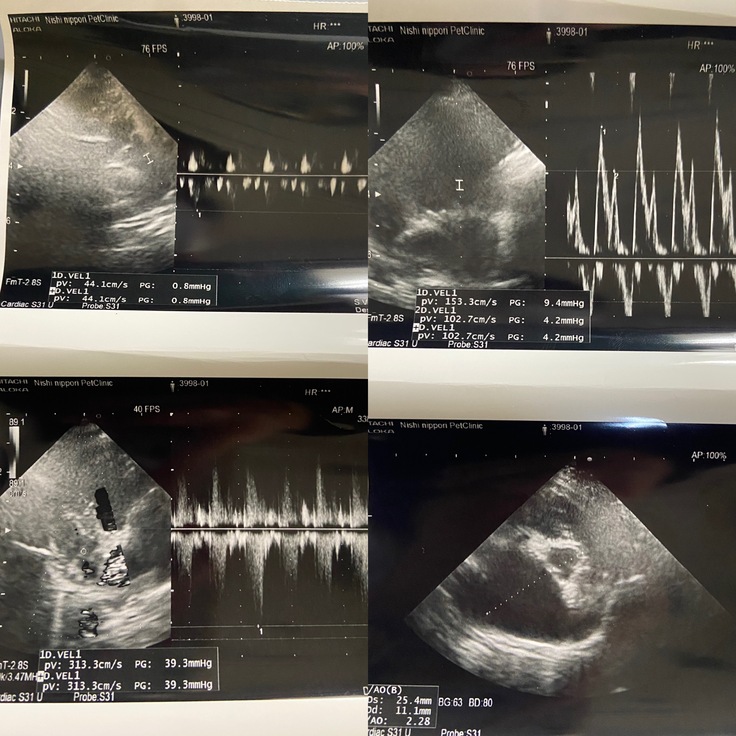

「僧帽弁閉鎖不全症(ステージC)」という心臓の病気で、2025年6月9日には肺水腫を起こしてしまいました。

ピニョンは2025年4月頃から咳がでていたので、かかりつけの病院に行ったところ僧帽弁閉鎖不全症と診断されました。

咳がひどくなってきて、座ったまま寝るようになりおかしいと思い、6月にセカンドオピニオンを受けたところ心臓は肥大していて、既に肺に水が溜まり肺水腫(心不全)を起こしていました。

正常な心臓と比べるとピニョンの心臓は肥大してしまっています。

僧帽弁閉鎖不全症には進行度によっていくつかステージがあります。

ピニョンは現在ステージCと診断されています。